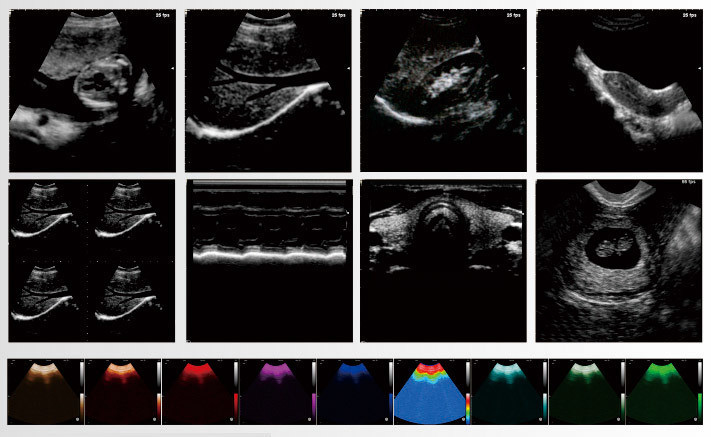

IMR Market Reports: Black and White B-Ultrasound Market is growing at a faster pace with substantial growth rates over the last few years and is estimated that the market will grow significantly in the forecasted period i.e. 2021 to 2027.